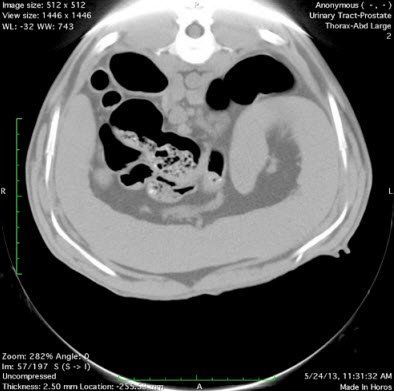

A computerized tomography scan, or CT scan, is far more detailed than a simple X-ray. CT machines utilize a variety of X-rays taken from different angles that are then processed by a computer to create accurate images of different cross-sections of the body. Bones, blood vessels, organs, and other soft tissues can all be closely examined through this non-invasive technology.

At South Seattle Veterinary Hospital, we use a CereTom Portable Small Animal CT scanner. This scanner is uniquely suited for dogs and cats and combines digital radiography and ultrasound technology to give attending physicians a complete picture of your pet's health.

Performing CT Scans provides a 3D view of the treatment area and quickly diagnoses conditions including: